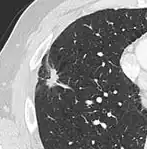

CT scan

For incidentally detected nodules on CT scan, Fleischner Society guidelines are given in table below. For multiple nodes, management is based on the most suspicious node.[8] These guidelines do not apply in lung cancer screening, in patients with immunosuppression, or in patients with known primary cancer.[8]